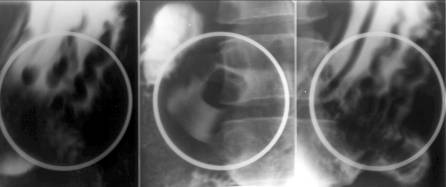

Incizura controlaterala reprezinta un spasm al musculaturii circulare care apropie marea curbura de mica curbura. Initial intermitenta, devine ulterior permanenta prin formarea, la acest nivel, a unui tesut fibros cicatricial, realizând o stenoza gastrica excentrica care biloculeaza asimetric stomacul (semnul indicatorului).

Gastrita hipertrofica acompaniaza leziunile principale. Poate fi localizata segmentar, în apropierea nisei, sau generalizata la întreg stomacul. În evolutia spre vindecare, pliurile devin convergente spre nisa realizând o imagine stelata.